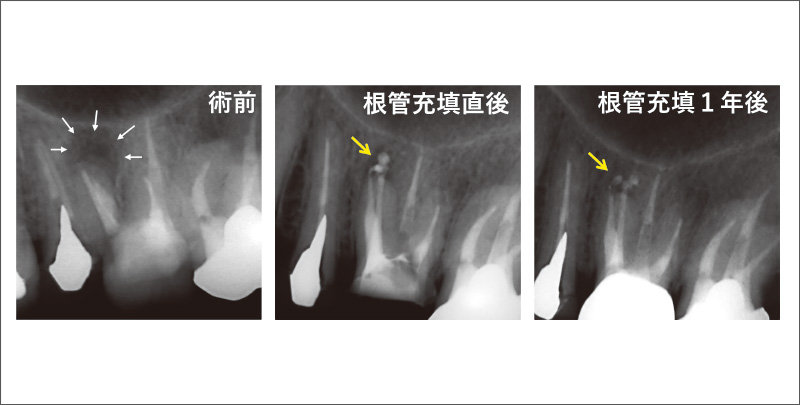

![[写真] 根尖孔が開大した根管への根管充填(27歳女性)](/academic/dentalmagazine/wp-content/uploads/sites/2/2025/09/194-1_photo10.jpg)

図10 根尖孔が開大した根管への根管充填(27歳女性)

根尖部に骨欠損(黒矢印)がみられ根尖孔は外開きだが、過不足なく充填され、6か月後には骨欠損は消失した。 -

![[写真] 樋状根への根管充填(59歳女性)](/academic/dentalmagazine/wp-content/uploads/sites/2/2025/09/194-1_photo13.jpg)

図13 樋状根への根管充填(59歳女性)

近心と遠心の根管をつなぐイスムスまでシーラーで封鎖され(青矢印)、1年後には骨欠損は消失した。